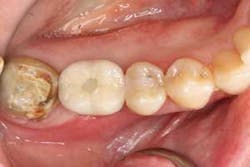

A 65-year-old female presented with a cement-retained implant crown No. 30 on an external hex implant, which became loose (figure 8). The crown had been in function for 15 years. Fortunately, the cement-retained crown was able to be removed, but it was still attached to its abutment and abutment screw (figure 9) and, therefore, was not able to be recemented.

Figure 8:Loose implant crown.